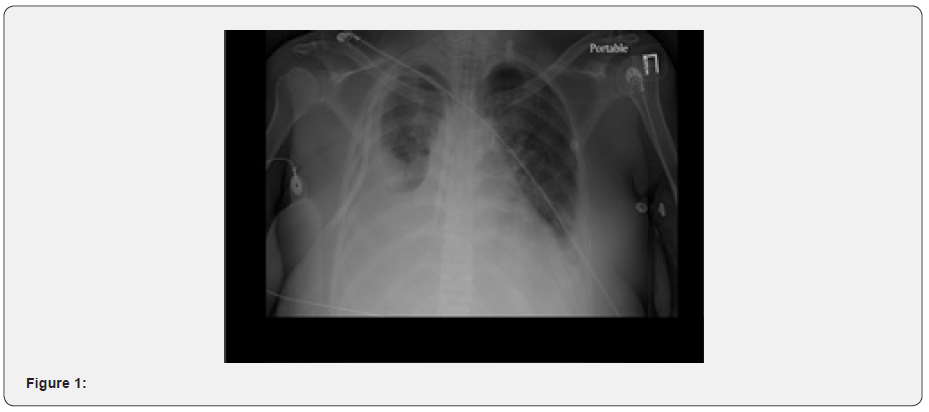

Lung exam showed bibasilar crackles with occasional wheezes. arterial blood gas was consistent with hypercapnia respiratory failure with pH: 7.13, PCO2: 81, HCO3: 23.1, SpO2: 98.8 and PO2: 164. Labs were significant Blood urea nitrogen: 22mg/dl, creatinine: 5.2mg/dl, estimated glomerular filtration rate: 9ml/min, microcytic anemia with hemoglobin: 6.5g/dl, white blood cells: 3700/cubic millimeter and Platelet: 104,000/cubic millimeter. Electrocardiogram was within normal limits. CT Head was unremarkable except for old lacunar infarcts in the pons. The patient was intubated and transferred to the intensive care unit on ventilator settings of tidal volume: 400, respiratory rate: 16, Peak end expiration pressure: 5 and fraction of inspired oxygen: 40. Chest X ray and CT showed bilateral pleural effusions (right greater than left) and underlying consolidation of the right basilar segments (Figure 1).